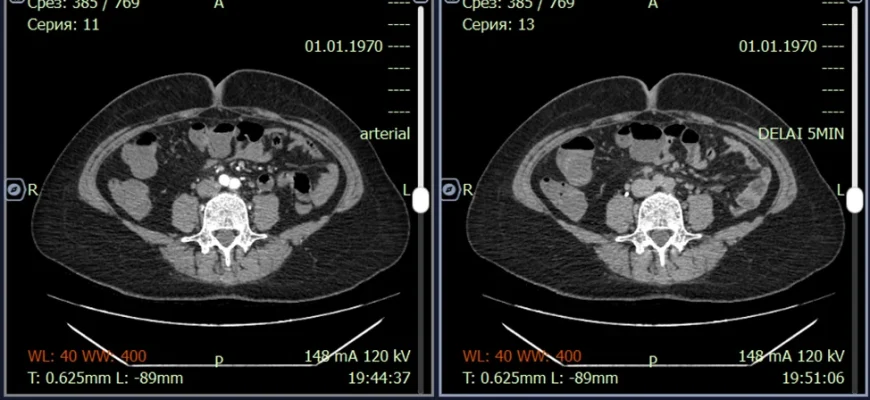

DICOM: От пикселя к диагнозу – Как мы разрабатываем системы анализа медицинских изображений В эпоху цифровой медицины, когда изображения стали неотъемлемой

ИИ в анализе медицинских изображений: Как технологии меняют здравоохранение В последние годы мы наблюдаем невероятный прогресс в области искусственного